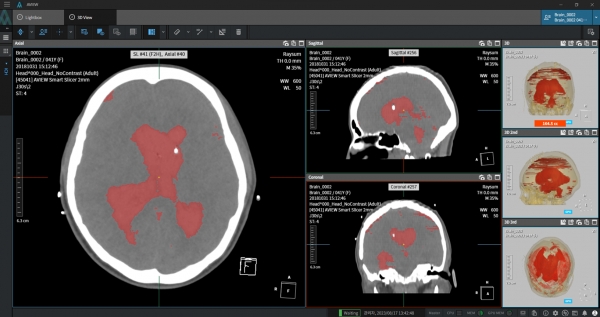

코어라인소프트가 오는 17~18일 광주 김대중컨벤션센터에서 개최되는 2025 대한응급의학회 춘계 학술대회(KSEM)에 참가해, 응급질환 영상 진단의 AI 활용 가능성과 임상 성과를 소개한다고 10일 밝혔다.

이번 학술대회에서 박준민 코어라인소프트 상무(CPO, 최고제품책임자)는 ‘의료 영상 인공지능의 임상 적용: 응급 현장의 가능성과 확장성’을 주제로 발표에 나설 예정이다. 박 상무는 응급 현장에서 뇌출혈, 폐색전증, 대동맥박리 등 중증 질환을 AI로 조기에 감별·진단한 실제 임상 사례와 함께, 영상의학과 전문의들과의 협업을 통해 축적된 기술 활용 경험을 공유한다고 알렸다.

특히 코어라인소프트는 학술대회 기간 동안 ▲AI 기반 뇌출혈 진단 소프트웨어 ‘AVIEW NeuroCAD’ ▲폐 질환 통합 분석 SW ‘AVIEW LCS Plus’ 중심의 의료진 컨설팅도 병행할 예정이다. AVIEW NeuroCAD(에이뷰 뉴로캐드)는 2024년 1월 국내 비급여 및 선별급여 시장에 진입했으며, 현재 원광대병원, 인하대병원, 일산백병원 등 20여 개 병원에서 도입돼 진료에 활용되고 있다.

회사에 따르면 해당 제품은 AI가 응급실에서 촬영된 뇌 CT 이미지를 실시간 분석하여 뇌출혈 의심 부위를 자동 탐지·표시함으로써, 의료진이 신속한 판단을 내릴 수 있도록 지원한다. 이를 통해 진단 속도와 정확도를 높이고, 환자의 생명을 좌우하는 ‘골든타임 확보’에 기여하고 있다는 평가를 받고 있다.

박준민 CPO는 “코어라인소프트는 영상의학과 의료진과의 긴밀한 협업을 바탕으로, 응급의료 환경에서 실제 사용할 수 있는 AI 기술 개발과 임상 적용에 앞장서고 있다”며, “이번 발표는 응급질환 영역에서 의료영상AI를 통한 임상적 유효성, 안전성에 대한 부가 가치를 공유하는 자리가 될 것”이라고 밝혔다.